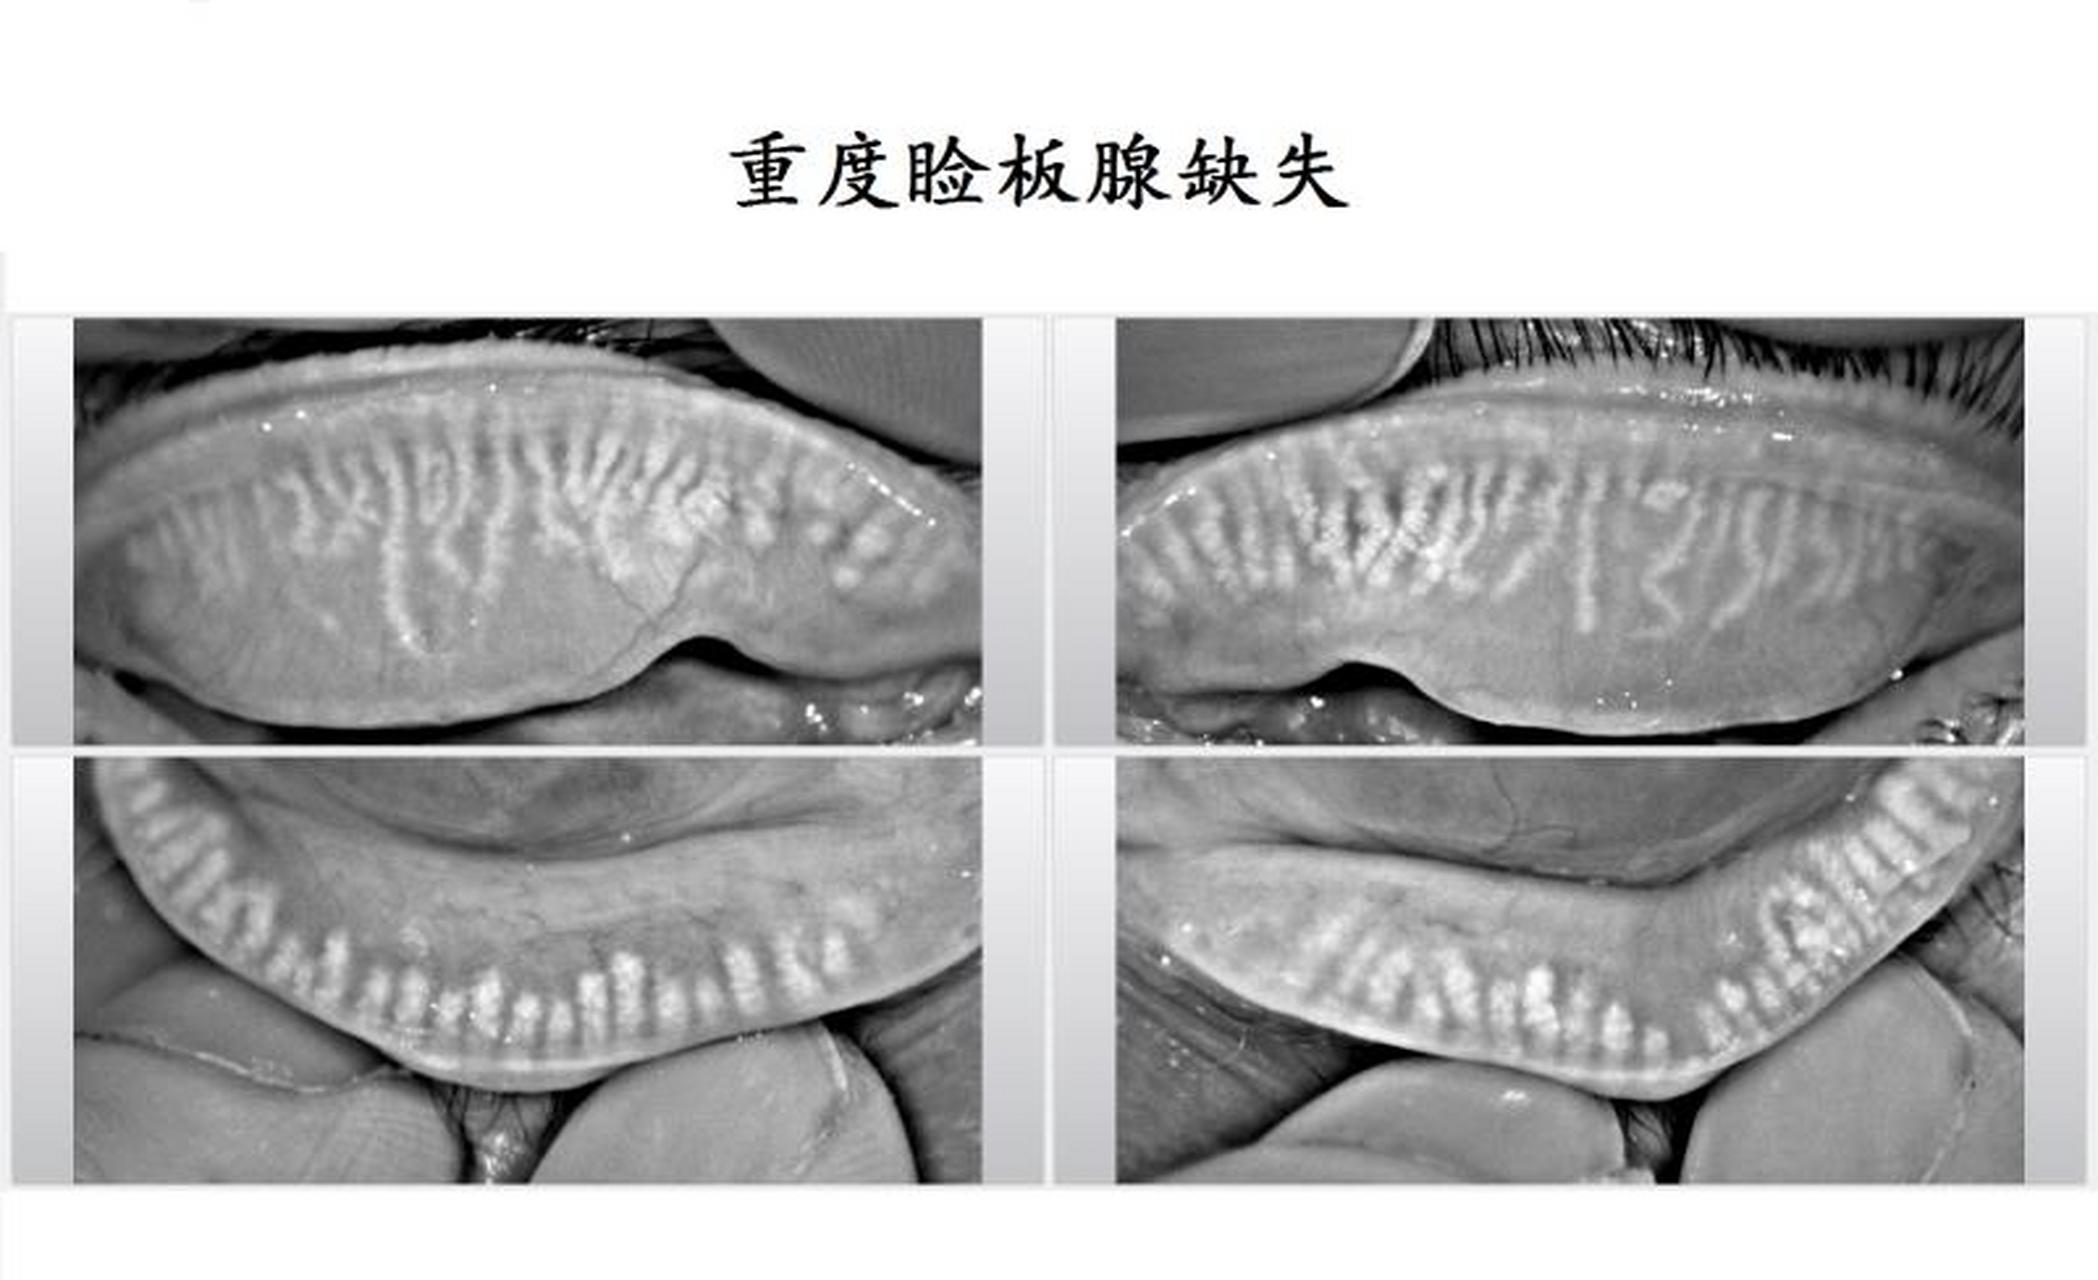

门诊一位睑板腺萎缩缺失特别严重的患者,接近下图.

图片尺寸2098x1280